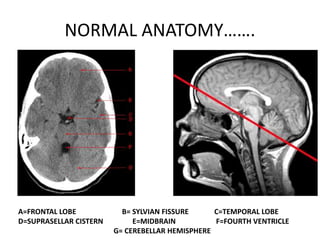

NORMAL ANATOMY…….

A=FRONTAL LOBE B= SYLVIAN FISSURE C=TEMPORAL LOBE

D=SUPRASELLAR CISTERN E=MIDBRAIN F=FOURTH VENTRICLE

G= CEREBELLAR HEMISPHERE